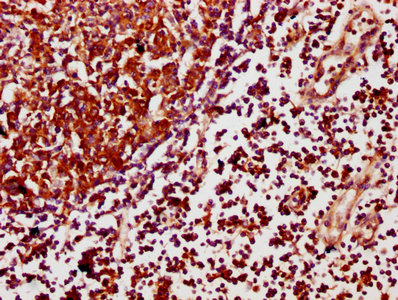

IHC image of CSB-PA754405LA01HU diluted at 1:500 and staining in paraffin-embedded human lymph node tissue performed on a Leica BondTM system. After dewaxing and hydration, antigen retrieval was mediated by high pressure in a citrate buffer (pH 6.0). Section was blocked with 10% normal goat serum 30min at RT. Then primary antibody (1% BSA) was incubated at 4°C overnight. The primary is detected by a biotinylated secondary antibody and visualized using an HRP conjugated SP system.